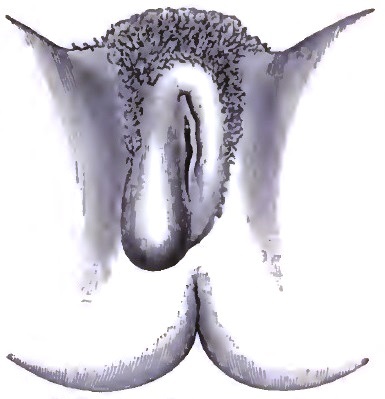

| 26. | IMPERFORATE HYMEN |